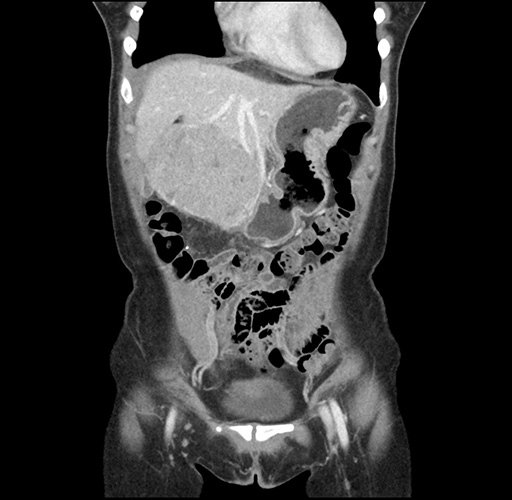

Imaging Analysis

Look through the patient's CT scan to identify any areas of concern for the necessary procedure.

Based on your CT findings, which issue(s) would give reason for "planned slowing down moment(s)" in this case?

Considering a standard left lateral sectionectomy procedure, what step(s) of the operation would you do differently in this case ?